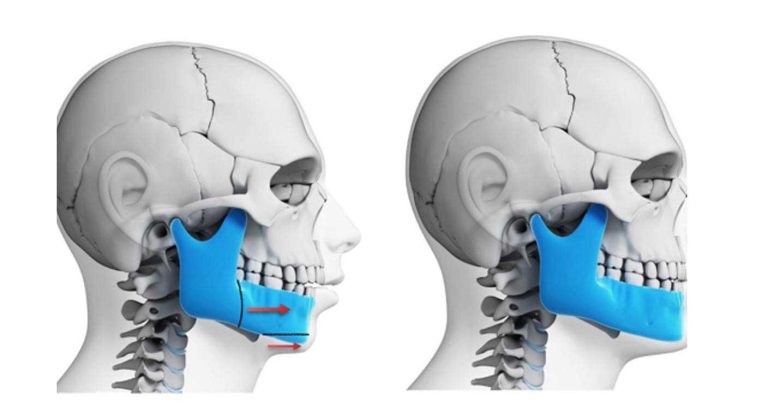

- جراحی فک بالا (استئوتومی Le Fort I)

در این جراحی، جراح برشی در استخوان فک بالا (ماگزیلا) ایجاد می کند تا کل فک بالا را به صورت یک واحد واحد به موقعیت صحیح خود حرکت دهد. - جراحی فک پایین (استئوتومی ساژیتال دو طرفه)

این رایج ترین نوع است که برای اصلاح موقعیت فک پایین (مندیبل) انجام می شود و فک به سمت جلو یا عقب حرکت داده می شود. - جراحی دو فک

در موارد پیچیده تر که هر دو فک بالا و پایین در موقعیت نادرستی قرار دارند، از درمان ارتودنسی به همراه جراحی دو فک استفاده می شود. - جنیوپلاستی (جراحی چانه)